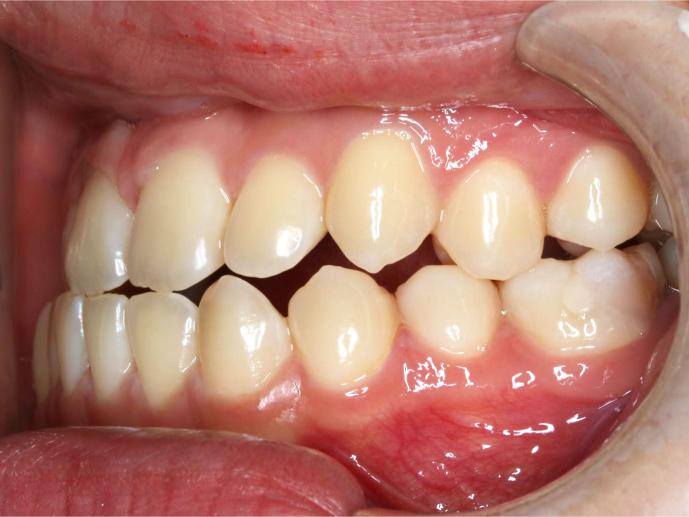

Before and After Images